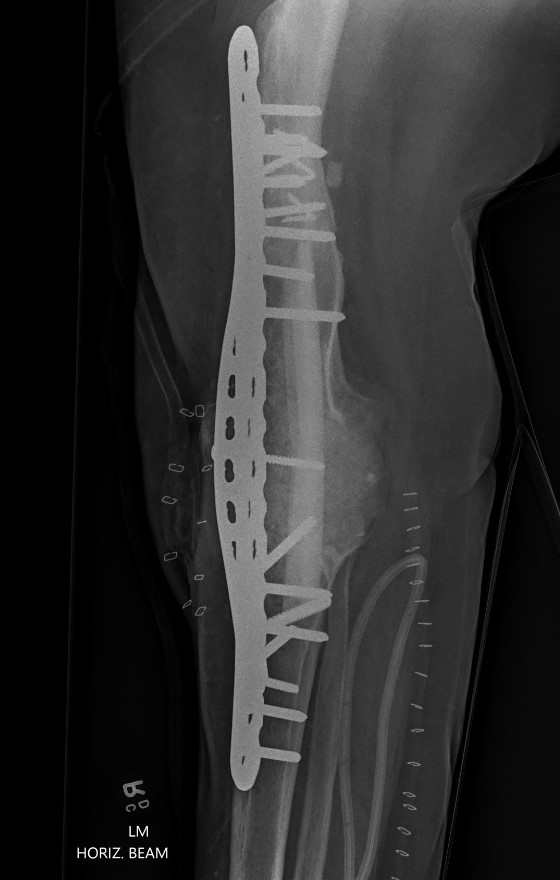

2. Double plating

Dual plates